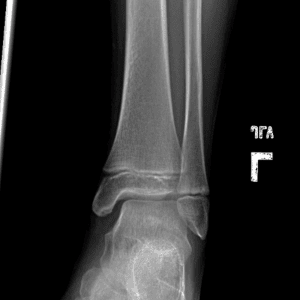

Pediatric Radiographs